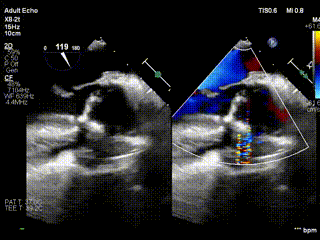

视频1:病例1术前食道超声示重度主动脉瓣反流

手术全程在全麻下进行,通过右侧股动静脉插管建立体外循环,保障术中血流动力学稳定;心肌保护采用 del-Nido 停跳液,经左右冠状动脉开口顺行灌注,并配合心脏表面冰屑降温,为精细操作创造条件。术中经食道超声实时监测显示:瓣膜修复后闭合良好,无反流信号;术后即刻评估提示,主动脉瓣跨瓣压差正常,左心室流出道通畅,手术达到 “解剖纠正 + 功能恢复” 的双重理想效果。

视频2:病例1术后心超示主动脉瓣无反流,eH 9.8mm,VBR 23.1mm,窦直径29.6mm,窦管交界 25.4mm。